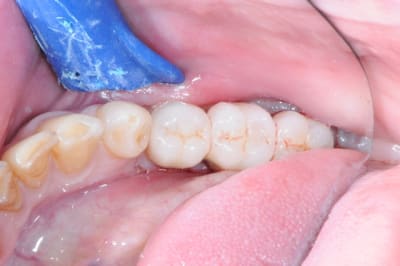

1 première consultation (septembre 2012)

2 rétro-alvéolaire (septembre 2012)

3 aspect (in vivo)

:)